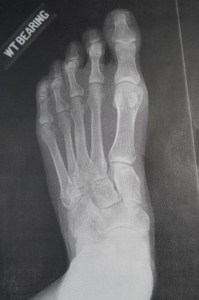

Before

Before surgery, you can’t see several digits because the bones are so deformed they’re stacked on top of each other.